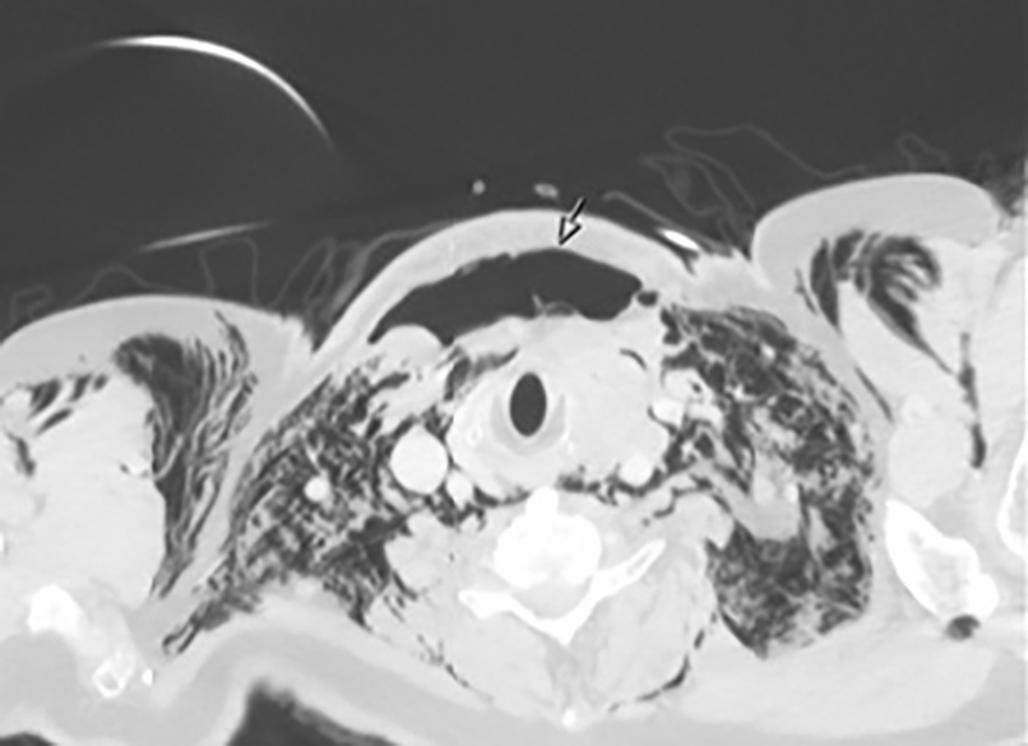

KASUISTIKK 1

En 72 år gammel kvinne oppsøkte fastlegen med nyoppstått 2x2 cm stor kul på halsen. Hun ble henvist til ultralydundersøkelse lokalt og senere ble det utført finnålsprøve samme sted, som ga mistanke om anaplastisk karsinom. Da hadde svulsten vokst til 8 cm. Hun ble henvist til regionsykehus og innlagt neste dag. Grovnålsbiopsier bekreftet anaplastisk thyreoideakarsinom. Pasienten hadde da utviklet heshet og smerter, men hadde ikke svelgvansker eller dyspné. Tumor i thyroidea var inoperabel, samt at hun hadde multiple små lungemetastaser. Det ble startet med strålebehandling to ganger daglig (1,5 GYx30-45) samt ukedose doksorubicin. Behandlingsrespons ble evaluert med CT-undersøkelse (Bilde 1). Det ble påvist BRAF (V600E) mutasjon, og etter fullført strålebehandling ble det startet med BRAF-/MEK hemmerne dabrafenib 75 mg x 1 og trametinib 1 mg x 1 en måned etter innleggelsen. Dosen ble økt etter ni dager. Tumor og metastaser på hals og i lunger viste komplett respons, og pasienten ble operert med venstresidig hemithyreoidektomi etter fem måneder. Det var betydelige adheranser og forandringer rundt thyroidea relatert til tidligere behandling. Endelig histologi viste kun enkeltliggende tumorceller i thyreoidealappen. Dabrafenib 100 mg x 2 og trametinib 2 mg x1 ble kontinuert med enkelte pauser på en til tre uker på grunn av nøytropen feber.

BILDE 1: Initial CT collum viste tumorstørrelse på 70x54 mm. CT undersøkelse en måned senere som var tre dager etter fullført strålebehandling viste tumor-reduksjon til 55x48mm. CT undersøkelse etter ytterligere tre måneder med tillegg av dabrafenib og trametinib viste at tumor hadde gått tilbake til tre cm i størrelse. Samtykke til publisering av røntgenbildene er innhentet fra pasientens ektemann da pasienten er død.